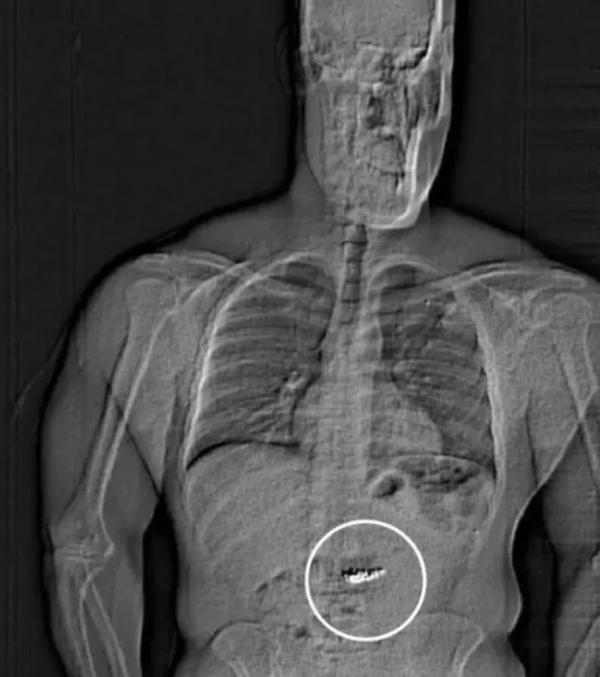

لكن أثناء وجوده في السجن، سأل جيلدر بشكل عفوي الموظفين إذا كان سيتم توجيه تهم له بشأن ما في معدته، بحسب ما تم نشره عن تقرير الاعتقال. ثم خضع جيلدر لفحص جسدي حيث تمكن المحققون من اكتشاف أجسام غريبة تمر عبر جهازه الهضمي.

وجاء في تقرير الاعتقال: «يُشتبه في أن هذه الأجسام الغريبة هي الأقراط المسروقة من «تيفاني آند كو»، لكن يجب جمعها من قبل مكتب شرطة مقاطعة ويلدون، ولا يمكن الجزم بأنه من حق الشرطة إخضاعه لجراحة بالقوة بهدف استخراج الألماس».